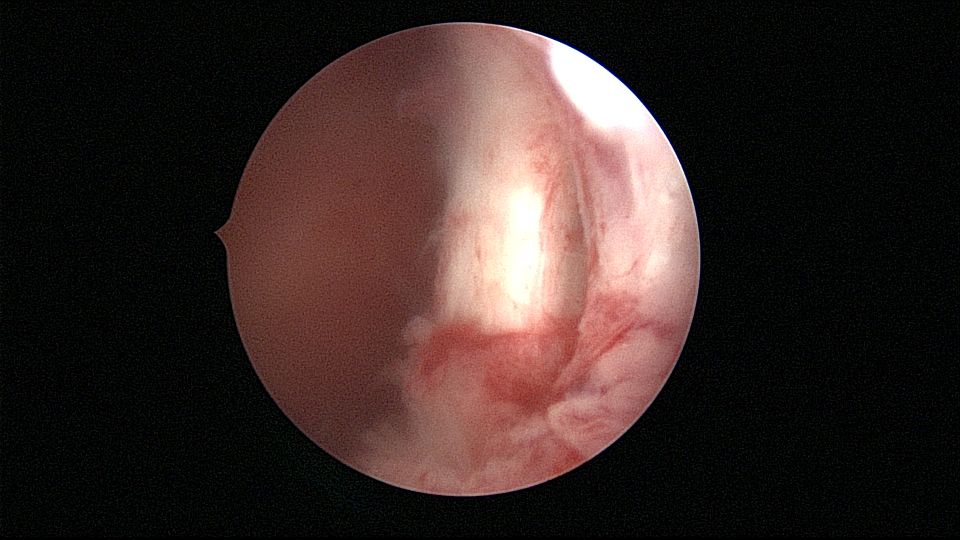

患者25岁,G1P0,停经52天,稽留流产,B超宫内偏右查见大小约2.4cmx1.0cmx1.7cm孕囊回声,形态规则,内可见直径约0.4cm的卵黄囊回声,未见胎芽,孕囊旁肌层最薄处厚约0.5cm,子宫中下段回声连续性欠佳,似可见一分隔回声。2021年7月宫腔镜探查,胚胎着床于宫腔前壁偏右,宫颈内口及宫腔左侧壁粘连。清除妊娠组织,单极电针分粘,恢复宫腔形态,双侧输卵管开口显露(第一次怀孕,宫腔粘连原因?)。2022年7月自然妊娠,2023年3月足月剖宫产分娩。2024年12月,外院人流术后1+月,宫内残留,与后壁肌层分界欠清,局部血流信号增多,到我院宫腔镜切除残留组织(后3张图片)。现患者30岁,G3P1。宫腔粘连常常不能阻止妊娠,但胚胎停育发生率增加。